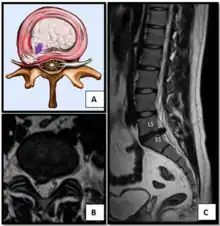

Herniated lumbar disc

The majority of spinal disc herniations occur in the lumbar spine (95% at L4–L5 or L5–S1).[20] The second most common site is the cervical region (C5–C6, C6–C7). The thoracic region accounts for only 1–2% of cases. Herniations usually occur postero-laterally, at the points where the annulus fibrosus is relatively thin and is not reinforced by the posterior or anterior longitudinal ligament.[20] In the cervical spine, a symptomatic postero-lateral herniation between two vertebrae will impinge on the nerve which exits the spinal canal between those two vertebrae on that side.[20] So, for example, a right postero-lateral herniation of the disc between vertebrae C5 and C6 will impinge on the right C6 spinal nerve. The rest of the spinal cord, however, is oriented differently, so a symptomatic postero-lateral herniation between two vertebrae will impinge on the nerve exiting at the next intervertebral level down.[20]

Lumbar disc herniations occur in the back, most often between the fourth and fifth lumbar vertebral bodies or between the fifth and the sacrum. Here, symptoms can be felt in the lower back, buttocks, thigh, anal/genital region (via the perineal nerve), and may radiate into the foot and/or toe. The sciatic nerve is the most commonly affected nerve, causing symptoms of sciatica. The femoral nerve can also be affected and cause the patient to experience a numb, tingling feeling throughout one or both legs and even feet or a burning feeling in the hips and legs.[21] A herniation in the lumbar region often compresses the nerve root exiting at the level below the disc. Thus, a herniation of the L4–5 disc compresses the L5 nerve root, only if the herniation is posterolateral.

Intradural disc herniation is a rare form of disc herniation with an incidence of 0.2–2.2%. Pre-operative imaging can be helpful for diagnosis, but intra-operative findings are required for confirmation.[25]

Narrowed space between L5 and S1 vertebrae, indicating probable prolapsed intervertebral disc - a classic picture.

• Magnetic resonance imaging is the gold standard study for confirming a suspected LDH. With a diagnostic accuracy of 97%, it is the most sensitive study to visualize a herniated disc due to its significant ability in soft tissue visualization. MRI also has higher inter-observer reliability than other imaging modalities. It suggests disc herniation when it shows an increased T2-weighted signal at the posterior 10% of the disc. Degenerative disc diseases have shown a correlation with Modic type 1 changes. When evaluating for postoperative lumbar radiculopathies, the recommendation is that the MRI is performed with contrast unless otherwise contraindicated. MRI is more effective than CT in distinguishing inflammatory, malignant, or inflammatory etiologies of LDH. It is indicated relatively early in the course of evaluation (<8 weeks) when the patient presents with relative indications like significant pain, neurological motor deficits, and cauda equina syndrome. Diffusion tensor imaging is a type of MRI sequence used for detecting microstructural changes in the nerve root. It may be beneficial in understanding the changes that occur after herniated lumbar disc compresses a nerve root, and might help in differentiating the patients that need surgical intervention. In patients with a high suspicion of radiculopathy due to lumbar disc herniation, yet the MRI is equivocal or negative, nerve conduction studies are indicated.[43] T2-weighted images allow for clear visualization of protruded disc material in the spinal canal.